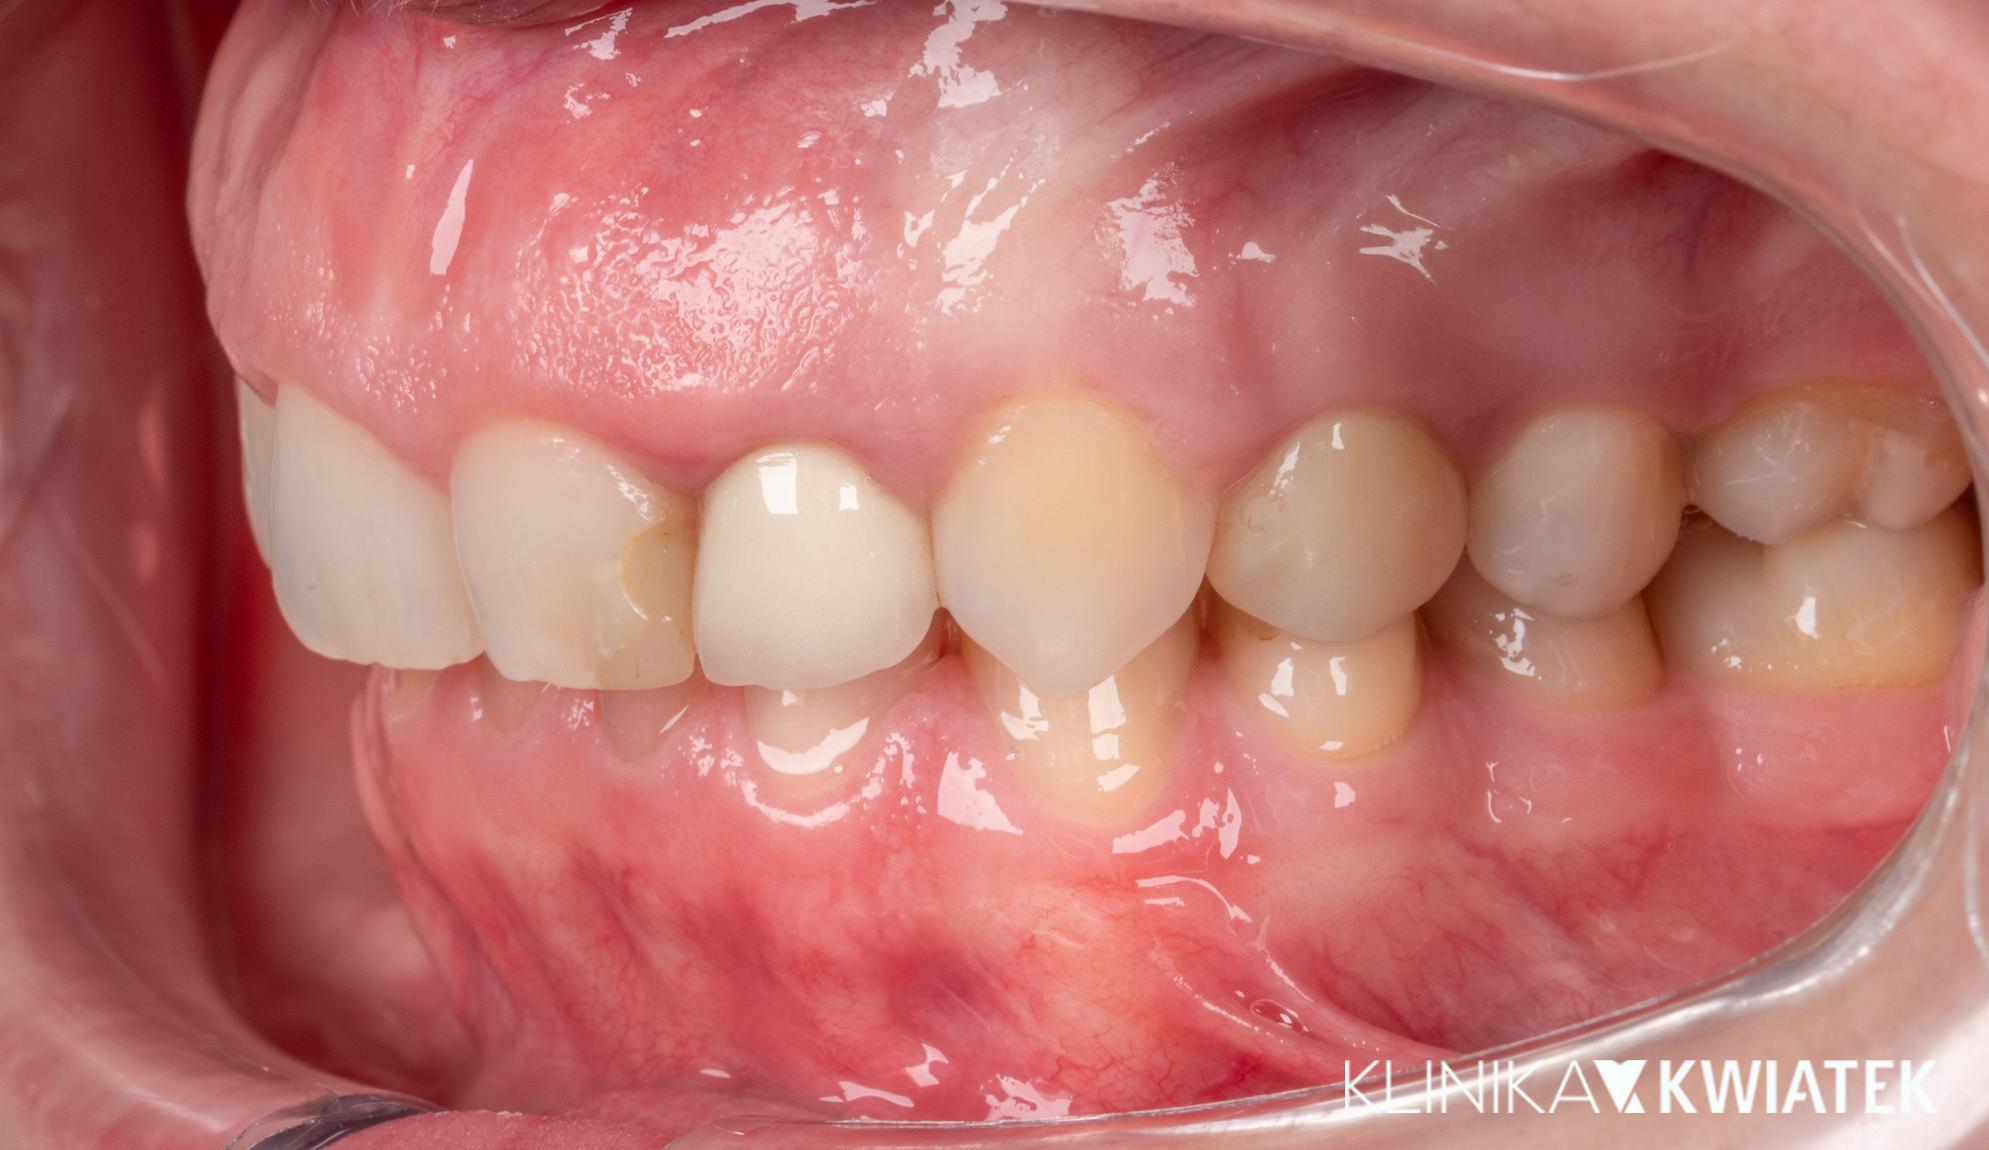

Kliniczna precyzja i estetyka – jak przywróciliśmy funkcję i piękno uśmiechu

Pacjentka zgłosiła się z wadą zgryzu, licznymi ubytkami i utraconymi zębami trzonowymi, co powodowało trudności w żuciu i estetyczne niezadowolenie. Leczenie obejmowało ekstrakcje, ortodoncję, implantację oraz kompleksową rekonstrukcję protetyczną. Po kilkunastu miesiącach terapii Pacjentka odzyskała pełną funkcję zgryzu i piękny, harmonijny uśmiech.